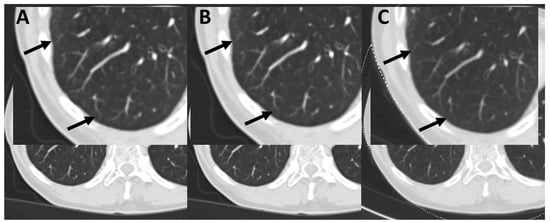

3.4. Subjective Image Quality